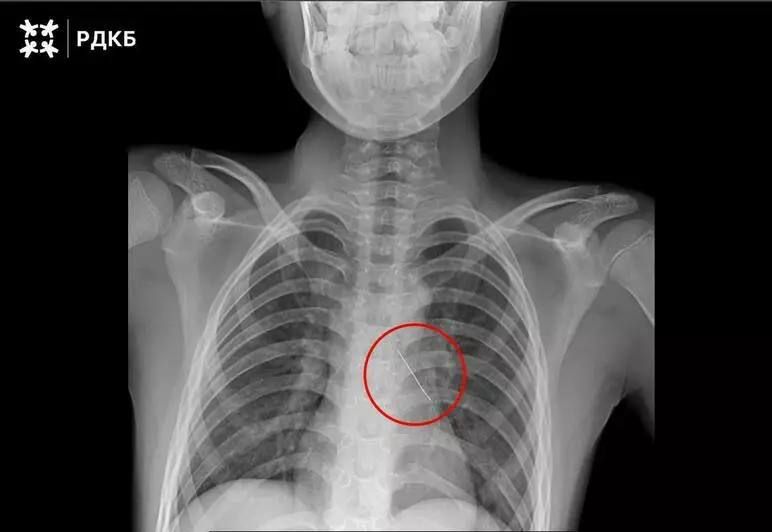

Ребёнок вдохнул булавку. Она пронзила бронх. В Калининграде извлечь инородное тело не смогли. Ребёнка в экстренном порядке доставили в Москву бортом санавиации.При поступлении в РДКБ мальчик мог говорить только шёпотом и испытывал сильные боли в...

Ребёнка в экстренном порядке доставили в федеральный центр бортом санавиации. До этого врачи по месту жительства провели телемедицинскую консультацию и попытались извлечь инородное тело, однако приняли решение о переводе пациента в...

Изогнутая французская булавка пронзила бронх, что могло привести к серьезным нарушениям дыхания и даже коллапсу легкого. 11-летнего пациента доставили в столицу бортом санавиации. Мальчик мог только шептать и испытывал сильные боли.Хирурги...